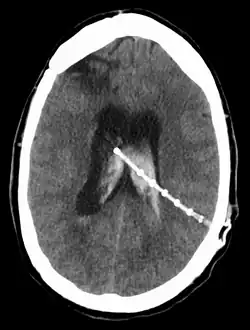

Dérivation du liquide cérébrospinal

Une dérivation du liquide cérébrospinal (ou shunt cérébral) est un dispositif implanté de façon permanente à l’intérieur de la tête et du corps pour évacuer l’excès de liquide du cerveau. Elle est couramment utilisée pour traiter l'hydrocéphalie, le gonflement du cerveau dû à une accumulation excessive de liquide céphalo-rachidien (LCR). Si rien n'est fait, l'excès de LCR peut entraîner une augmentation de la pression intracrânienne (PIC), ce qui peut provoquer un hématome intracrânien, un œdème cérébral, un écrasement du tissu cérébral ou une hernie[1]. Le drainage assuré par une dérivation peut atténuer ou prévenir ces problèmes chez les patients souffrant d'hydrocéphalie ou de maladies associées.

Les dérivations se présentent sous diverses formes, mais la plupart d'entre elles sont constituées d'un boîtier de valve relié à un cathéter dont l'extrémité inférieure est généralement placée dans la cavité péritonéale. Les principales différences entre les dérivations résident généralement dans les matériaux utilisés pour les construire, les types de vannes utilisées et le fait que la vanne soit programmable ou non[2].

L'emplacement de la dérivation est déterminé par le neurochirurgien en fonction du type et de l'emplacement du blocage provoquant l'hydrocéphalie. Tous les ventricules cérébraux sont candidats à la dérivation. Le cathéter est le plus souvent placé dans l'abdomen, mais d'autres emplacements incluent le cœur et les poumons. les dérivations peuvent souvent porter le nom de la voie utilisée par le neurochirurgien. L'extrémité distale du cathéter peut être située dans à peu près n'importe quel tissu comportant suffisamment de cellules épithéliales pour absorber le LCR entrant. Ci-dessous quelques plans de routage courants pour les dérivations cérébrales :